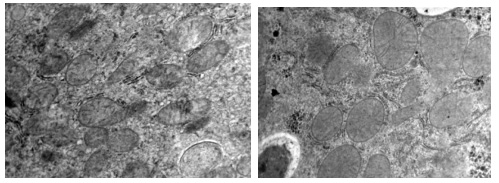

案例 不同組小鼠細胞電鏡圖(15000×)